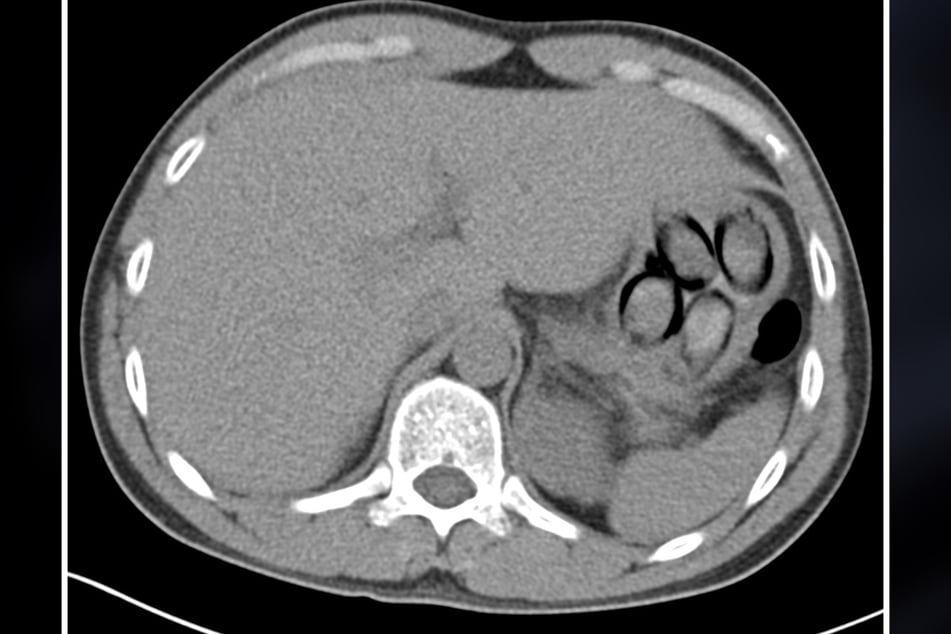

Auf einer dort angefertigten Röntgenaufnahme waren dann "mehrere Drogenpäckchen klar zu erkennen", berichtet Jens Ahland, Sprecher des Kölner Hauptzollamts, und ergänzt: "Insgesamt schied der Mann unter Überwachung sieben sogenannte Bodypacks mit insgesamt mehr als 100 Gramm Kokain aus."